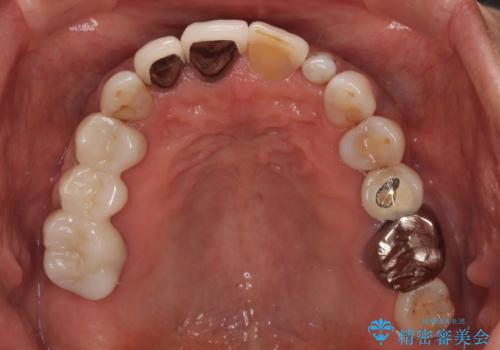

- 矮小歯である前歯がしみるとのことで来院された患者様です。

上顎前歯の歯肉ラインにエナメル質の欠損が認められ、そこが原因で冷たいものがしみている状態でした。

歯の大きさが小さいこと、隣の歯や反対側のセラミッククラウンの境目が見えていることなどから、前歯4本あるいは6本に対して、オールセラミッククラウンによる補綴治療をご提案しました。